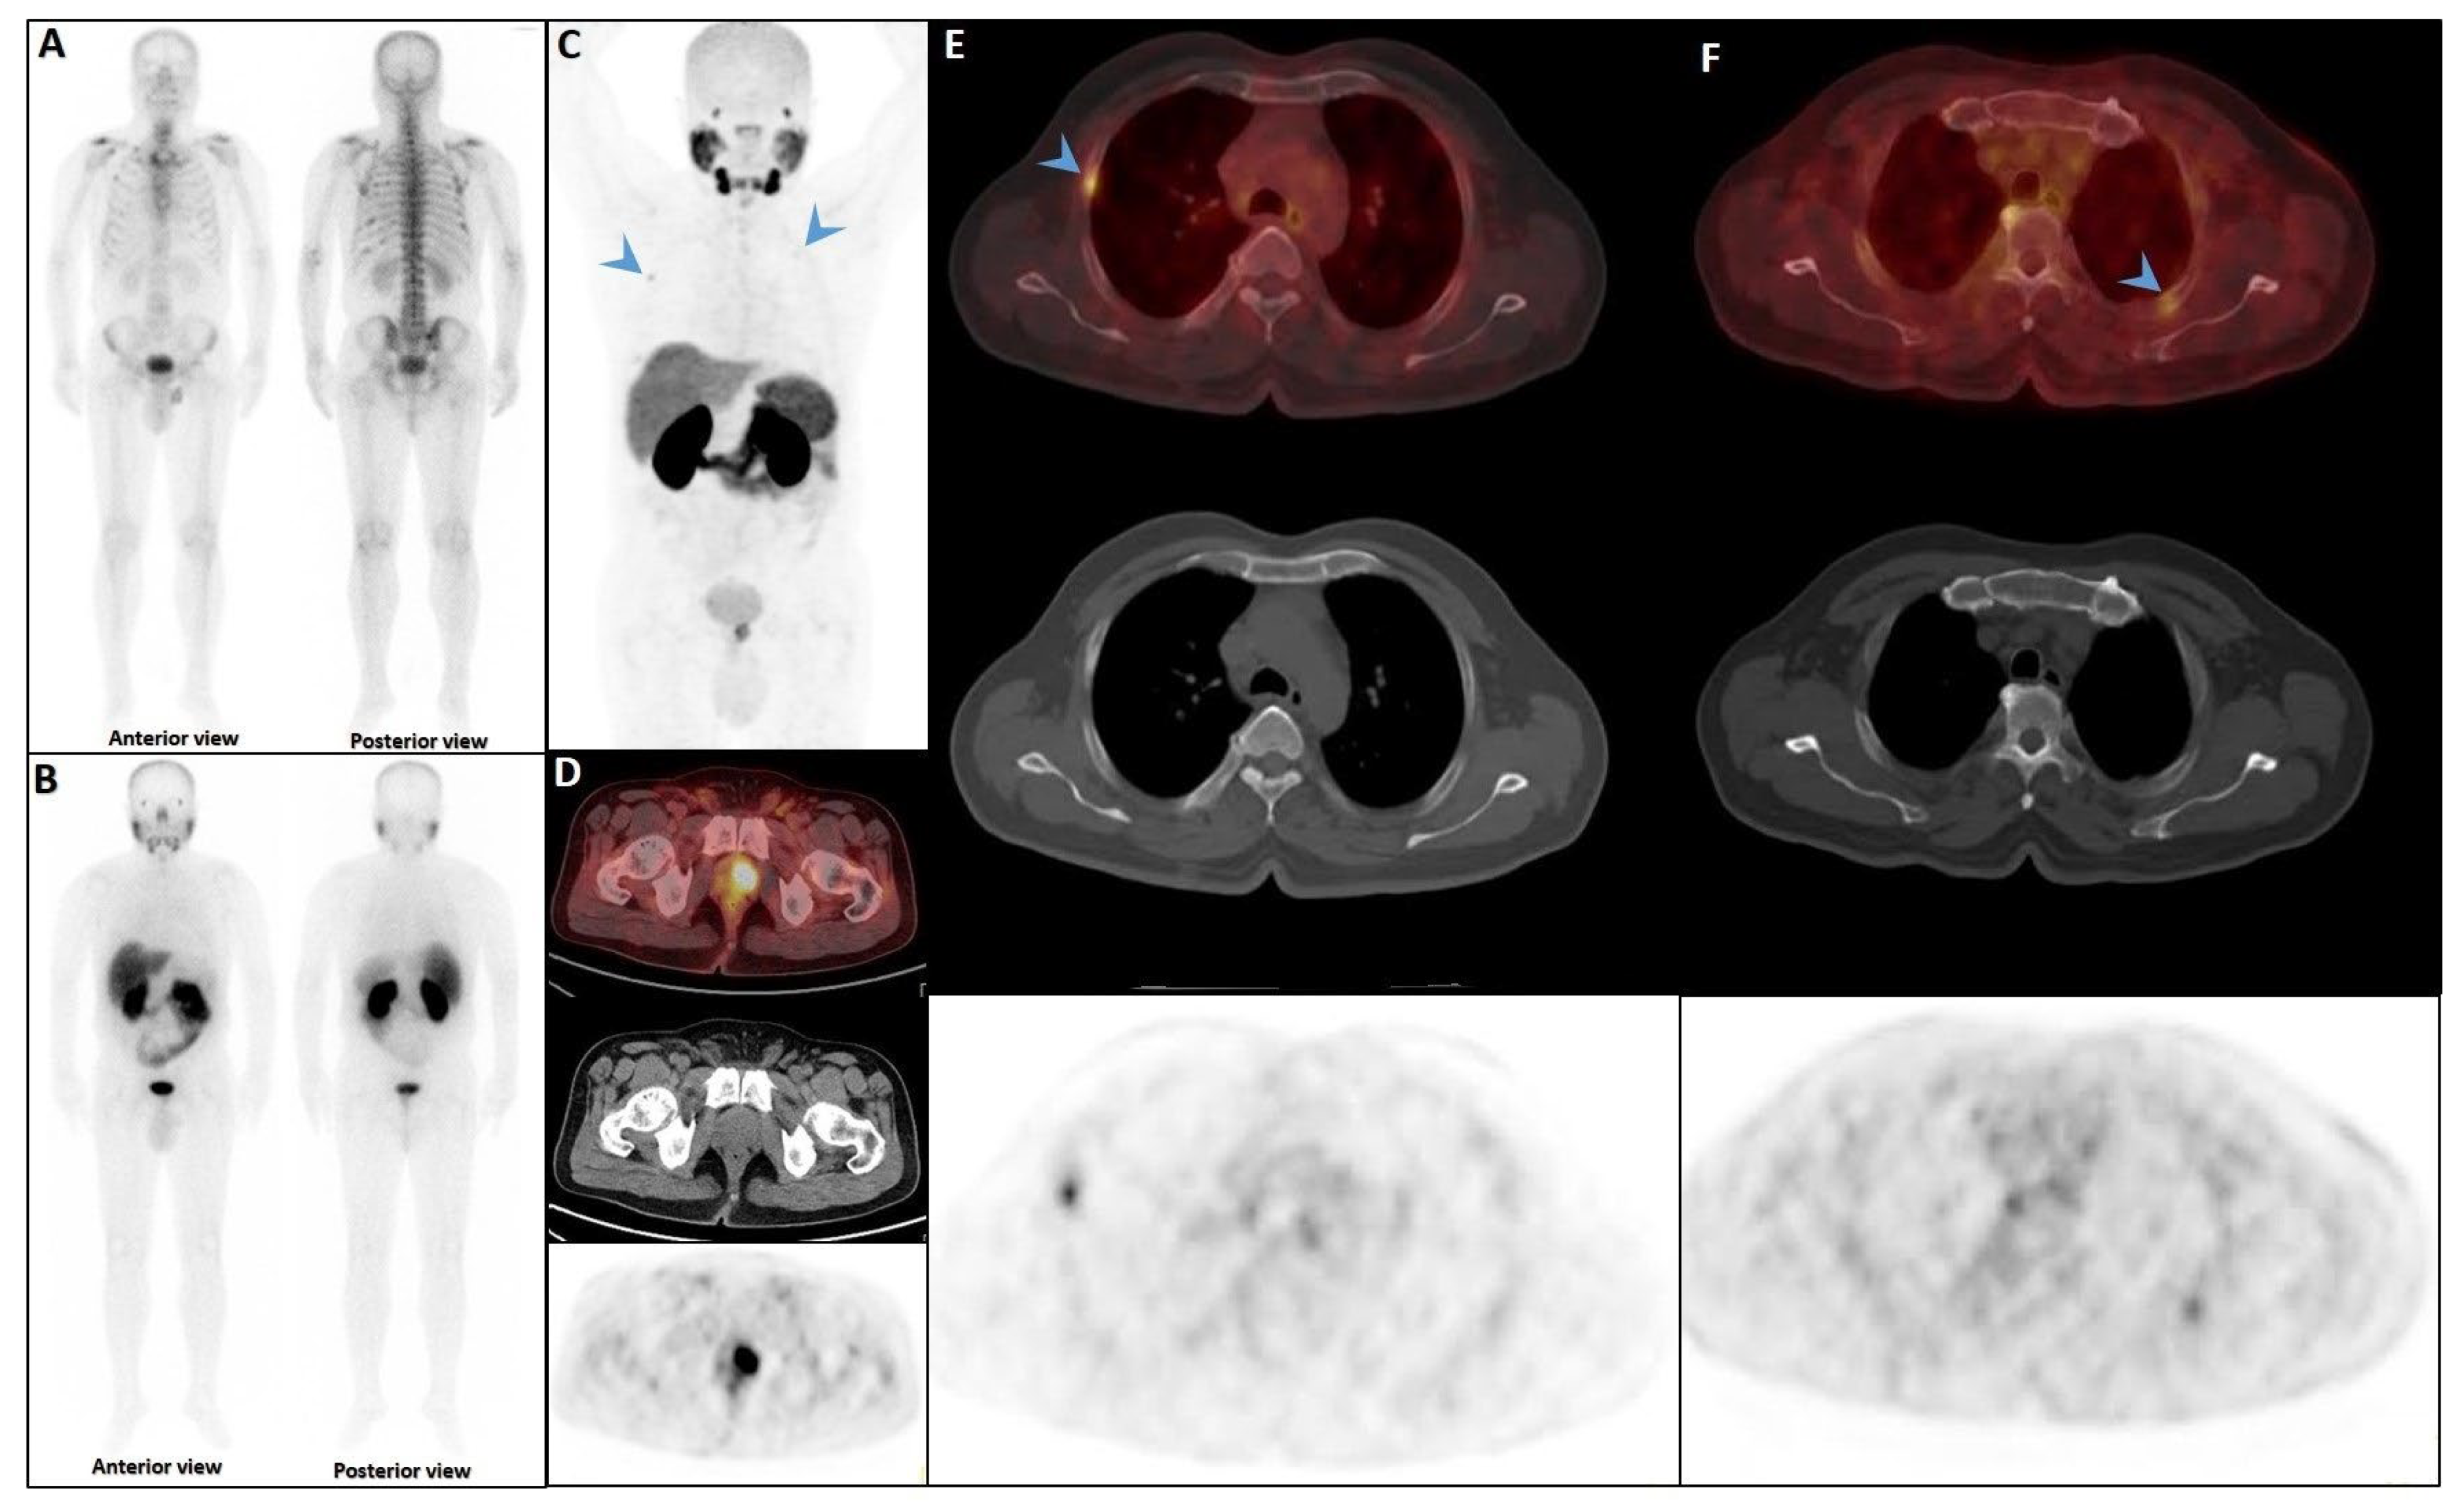

Figure 2.

Early phase of metastases without clear sclerotic changes in the bone. (A) 70-year-old man with elevated PSA was recently diagnosed with prostate adenocarcinoma (all cores positive with Gleason score 5 + 4) and referred for staging. The whole-body 99mTc-PSMA scan (A,B) and SPECT/CT showed multiple PSMA-avid skeletal metastases, most of which showing no/minimal density changes (C–F).

Figure 3.

False positive findings in bone scintigraphy due to rib fractures. A 78-year-old man with prostate adenocarcinoma (biopsy Gleason score 4 + 4, serum PSA = 56.8 ng/mL) was referred for staging. Whole-body bone scan revealed two consecutive focal osteoblastic activities in the lateral arc of the ribs on the right side (A,B). 99mTc-PSMA SPECT/CT (C) revealed increased tracer uptake in the prostate gland (D), multiple metastatic lymphadenopahies on the left side of pelvis and para-aortic regions (red arrow, (E)). Moreover, fractures in the right 6th and 7th ribs showed no PSMA avidity (white arrowheads, (F,G)).